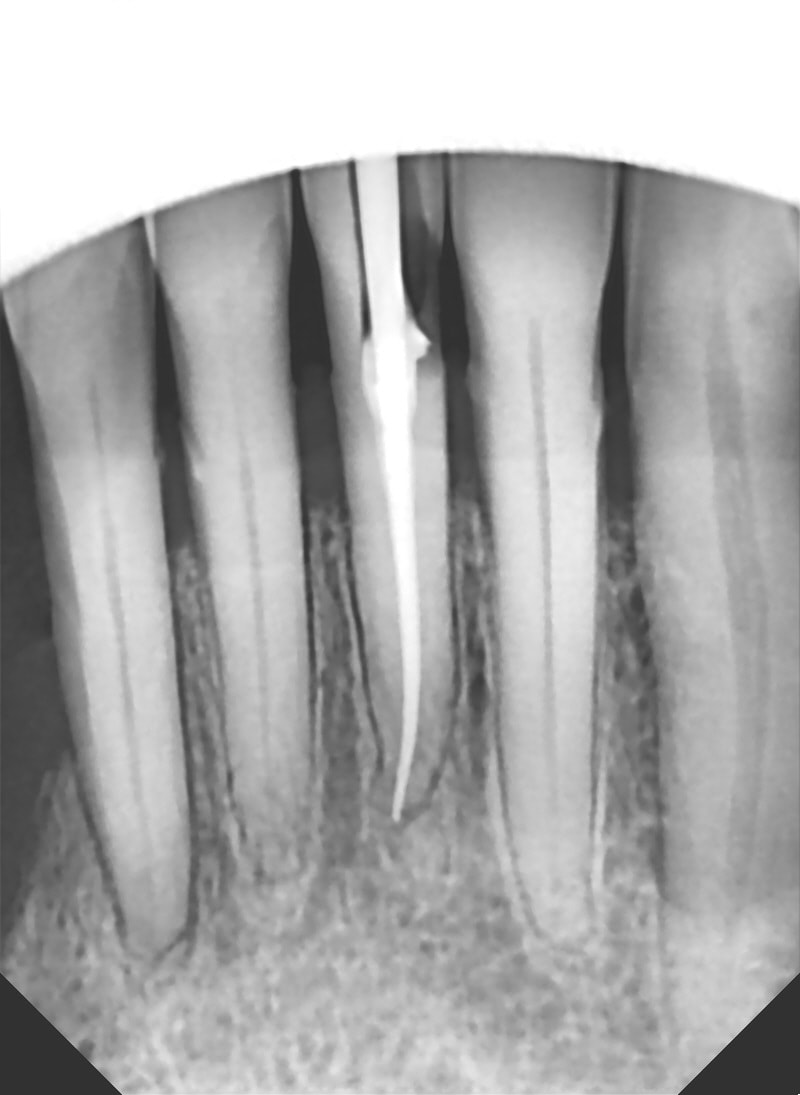

tu aurais une radio des dents restantes ?

voici le cliché

Ok, on a encore un rapport couronne/racine de 1/1 environ. Même si la 42...